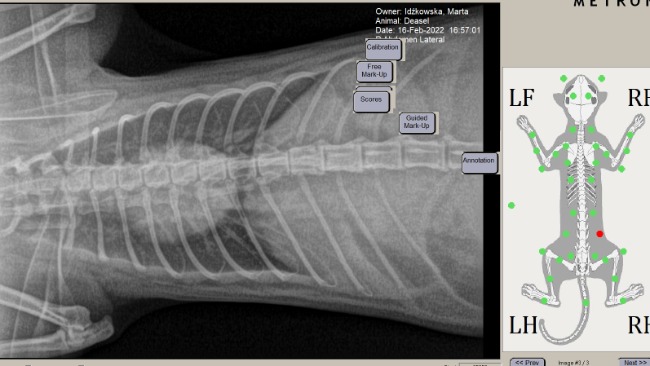

Znowu się zaczęło tylko objawy trochę się zmieniły. Zamiast kataru i kichania pojawiły się duszności, ciężki oddech i języczek na wierzchu. Więc znowu weterynarz. Diagnoza: podejrzenie astmy. Dostaliśmy skierowanie na prześwietlenie płuc. Wyszło nie za dobrze widoczne białe punkty w płucach.

Podejrzenie płynu w oskrzelach i płucach. Kolejne skierowanie: rektoskopia czyli badanie endoskopowe w celu pobrania i zbadania płynu. Czas oczekiwania miesiąc...

Rektoskopia wykazała zwężenie wejścia do oskrzeli, przekrwienie czyli zmiany typowe dla infekcji bakteryjnej. Dzięki bogu nie wykryto płynu w oskrzelach i płucach.

It started again only the symptoms changed a little. Instead of a runn ynose and sneezing, there was shortness of breath, heavy breathing .So vet again. Diagnosis: suspected asthma. We got a referral for alung x-ray. It turned out not well visible white spots in the lungs.

Suspicionof fluid in the bronchi and lungs. Rectoscopy and endoscopic examination to collect and examine the fluid. Waiting time one month...

Rectoscopys howed a narrowing of the bronchial entrance, hyperemia. Changes typical of a bacterial infection. Thank goodness no fluid was found in the bronchi and lungs.